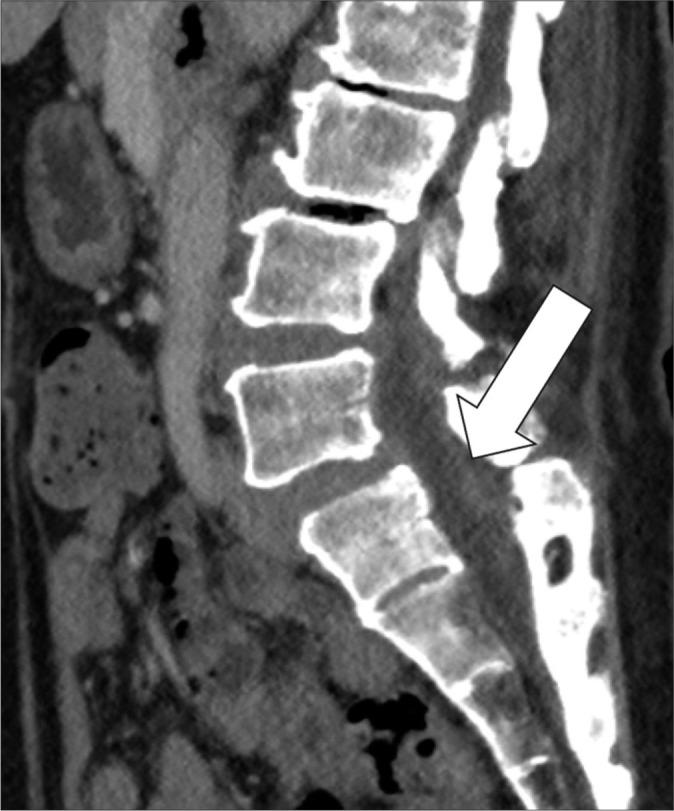

Facet joint septic arthritis is a rare; yet, severe spinal infection often misdiagnosed due to its non-specific clinical presentation and radiological mimickers. This case series illustrates various clinical presentations, imaging features, and outcomes of patients with facet joint septic arthritis. We demonstrate different disease stages to aid clinicians and radiologists in recognizing this condition. Key diagnostic pitfalls are also discussed to enhance diagnostic accuracy in clinical practice.

小关节化脓性关节炎较为罕见;然而,由于其非特异性临床表现及影像学上的相似表现,这种严重的脊柱感染常被误诊。本病例系列阐述了小关节化脓性关节炎患者的各种临床表现、影像学特征及治疗结果。我们展示了不同的疾病阶段,以帮助临床医生和放射科医生识别这种疾病。还讨论了关键的诊断误区,以提高临床实践中的诊断准确性。